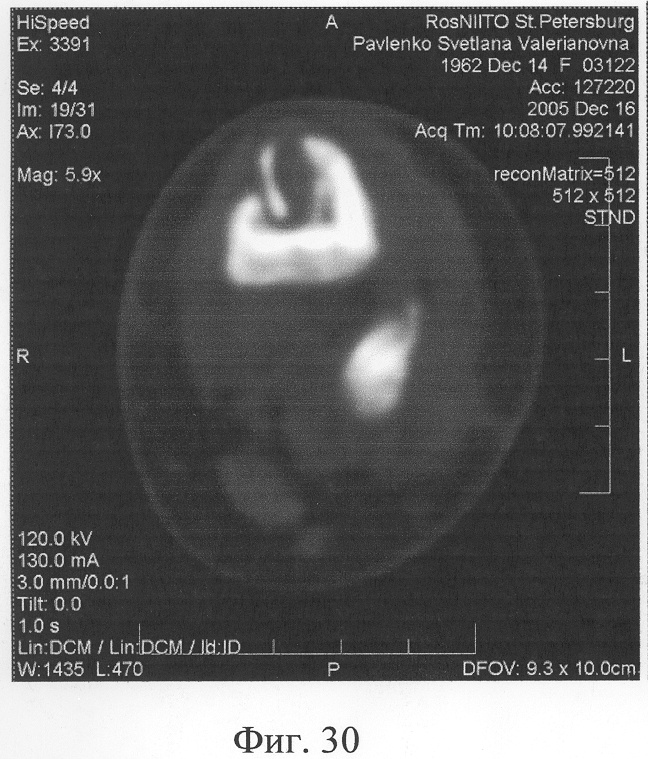

Аппарат внешней фиксации с левой голени демонтирован через 3 месяца после операции при клинико-рентгенологической картине сращения перелома. Аппарат внешней фиксации с правой голени демонтирован через 7 месяцев после операции при клинико-рентгенологической картине сращения перелома (фиг.20-25 – результат лечения). При рентгенологическом и томографическом контроле в трансплантатах отмечалось постепенное нарастание плотности костной ткани с формированием костной мозоли на всем протяжении между трансплантатом и костными фрагментами (фиг.26-29 – динамика данных компьютерной томографии правой голени: отмечается нарастание плотности костной ткани в области трансплантатов и формирование регенерата между смещенным трансплантатом и костными фрагментами; фиг.30-33 – динамика данных компьютерной томографии левой голени: отмечается нарастание плотности костной ткани в области трансплантатов и формирование регенерата между трансплантатом и костными фрагментами).